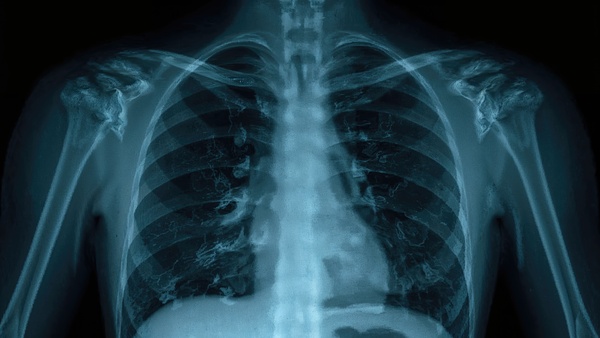

Un article publié dans la Revue Radiology met en lumière l’essor fulgurant de l’intelligence artificielle en imagerie thoracique.

• Interprétation assistée des radiographies et TDM thoraciques

• Détection automatisée des nodules pulmonaires, embolies ou pneumothorax

• Dépistage opportuniste des maladies non ciblées